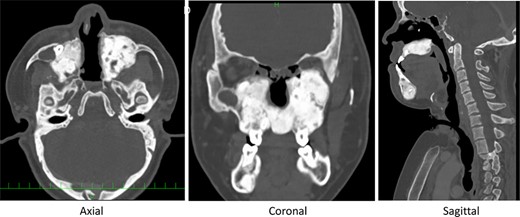

Preoperative computed tomography (CT) shows severe bone formation with inversed teeth (arrow heads); space between nose and pharynx was narrow.